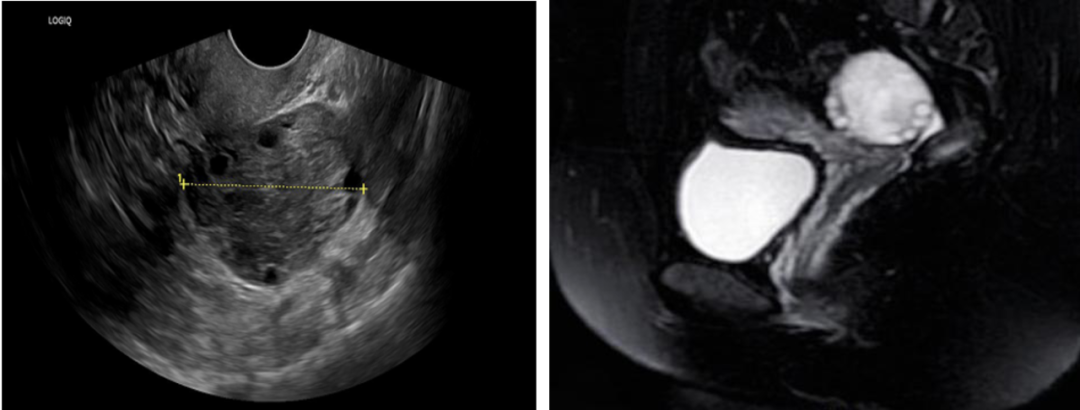

45天前毛毛突发左下腹剧烈疼痛,外院超声提示左附件区7cm“包块”,妇科检查左附件区压痛。她连续口服了抗生素足足5周,期间腹痛虽是缓解了,但一直有痛感,复查超声“包块”直径从7cm→6cm→4cm。9天前也就是停抗生素1天的时候,她的腹痛就加重了。毛毛百思不得其解,遂决定来浙大妇院看看。完善超声和MRI检查后,医生并没有发现她有卵巢囊肿和盆腔包块之类的,仅是左卵巢大,直径达8cm,周边有多量卵泡,妇科检查左下腹部确有压痛,符合盆腔炎诊断,可是经过整整5周的抗炎治疗竟然都不能治愈。吴再归医生内心疑惑了,思考片刻决定将其收住院。

B超和MRI检查提示卵巢增大